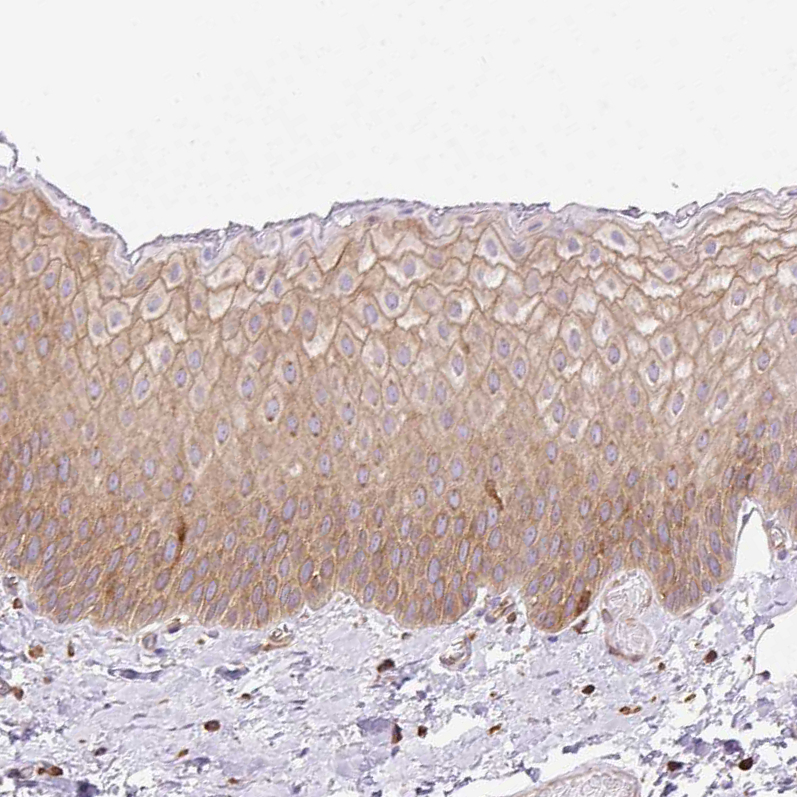

Immunohistochemistry analysis in human colon and liver tissues using HPA054246 antibody. Corresponding DNM2 RNA-seq data are presented for the same tissues.